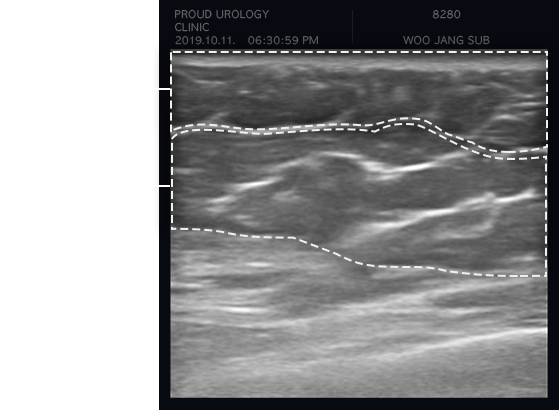

초음파를 통한 구분

하이스트는 고해상도 이미지를 구현하는 첨단 정밀 초음파

진단기(E-CUBE)를 통해

방사선 노출 없이 안전하게

유선조직 증식 여부를 정밀 검사합니다.